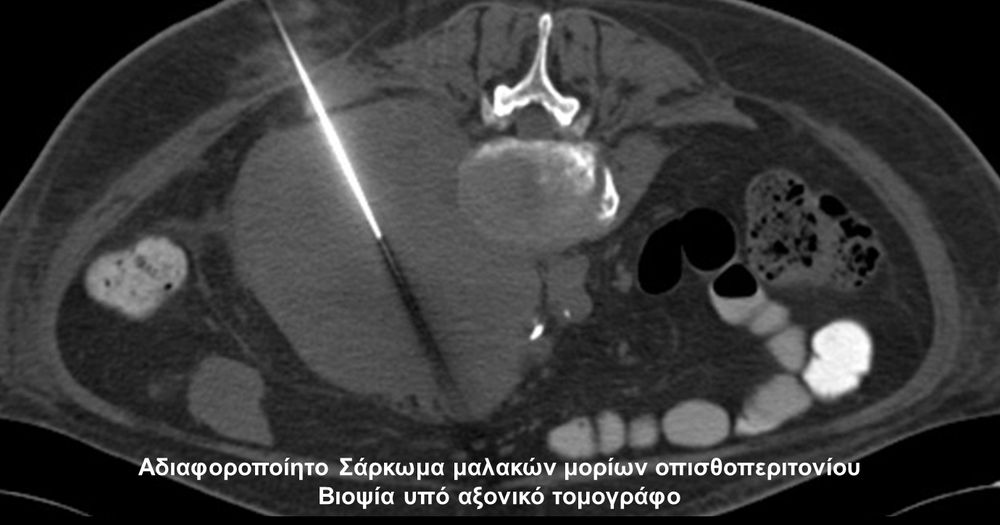

Η οστική βιοψία και η βιοψία όγκων μαλακών μορίων χρησιμοποιείται για την ιστολογική διάγνωση αλλοιώσεων (καλοήθων - κακοήθων / πρωτοπαθών ή μεταστατικών) ή για τη λήψη υλικού προς καλλιέργεια ώστε να αναδειχθεί το μικρόβιο που προκαλεί τη λοίμωξη του μυοσκελετικού συστηματος (πχ σπονδυλοδισκίτιδα). Η βιοψία υπό συνεχή απεικονιστική καθοδήγηση συμβάλλει στην υψηλή ακρίβεια τοποθέτησης της βελόνης εντός της βλάβης με ασφαλή προσπέλαση. Η χρήση σύγχρονων ομοαξονικών συστημάτων βιοψίας (coaxialtechnique) επιτρέπει την λήψη πολλαπλών δειγμάτων με μια μόνο παρακέντηση.